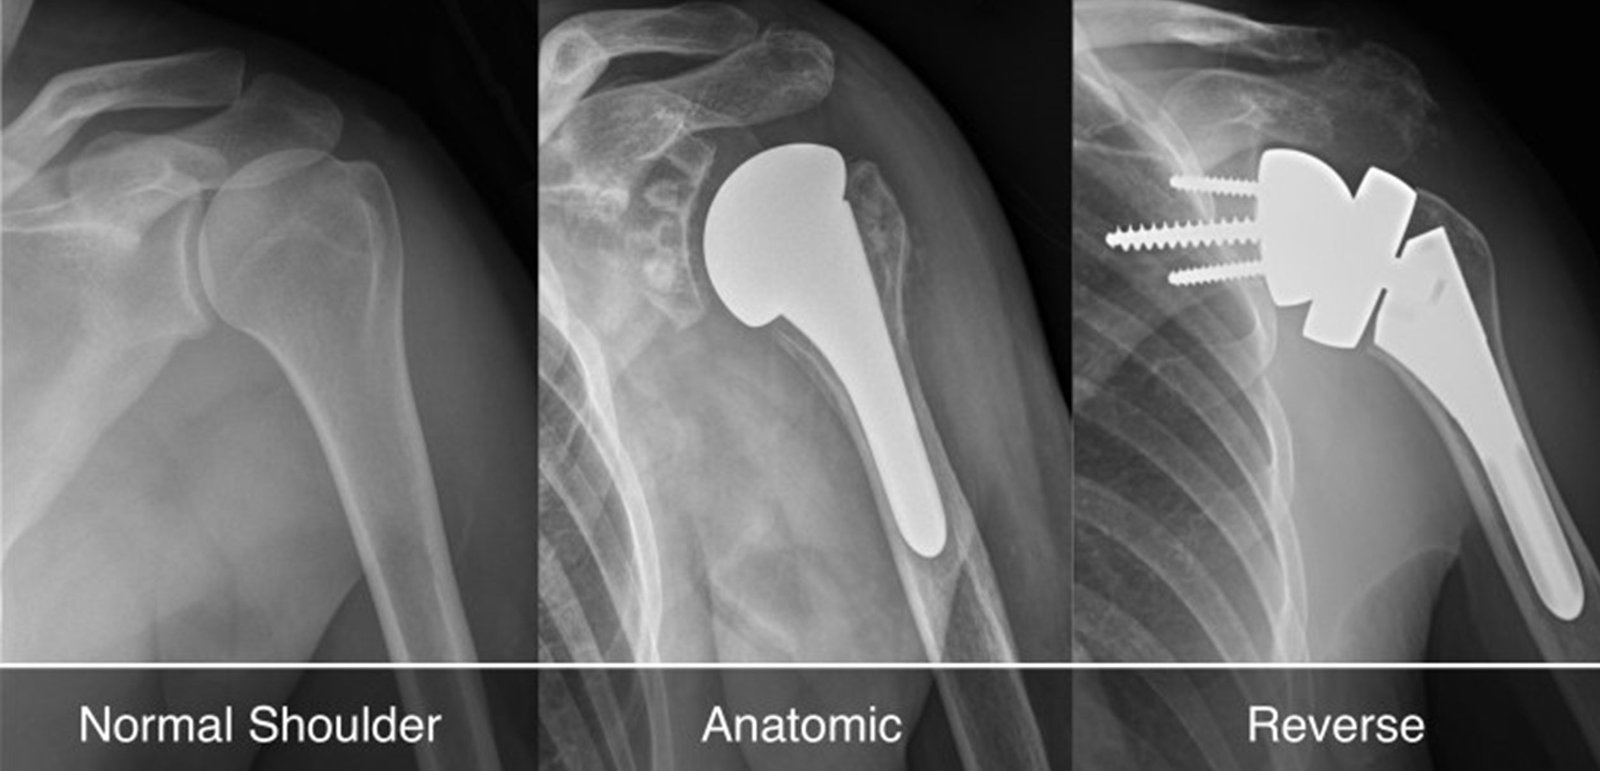

Unlike total shoulder replacement, which replaces both the ball and socket, resurfacing shoulder arthroplasty involves capping the damaged ball of the joint with a smooth, metal prosthesis. This approach is less invasive, preserves more bone, and is often ideal for younger, active patients with localized joint damage.